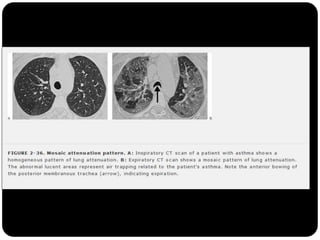

Perfusão em mosaico ( X vidro fosco)

O que foivisto até agora?  Cistos (LAM, Histiocistose de Langerhans, PIL)  Bolhas  Cavidades (diss. hemat. de infecção, neoplasia, TB, gran. Wegerner)  Enfisema (centrolobular)  Padrões e sinais torácicos Sinal de Westermark Sinal da corcova de Hampton Sinal de árvore em brotamento Perfusão em mosaico ( X vidro fosco) Faveolamento - fibrose